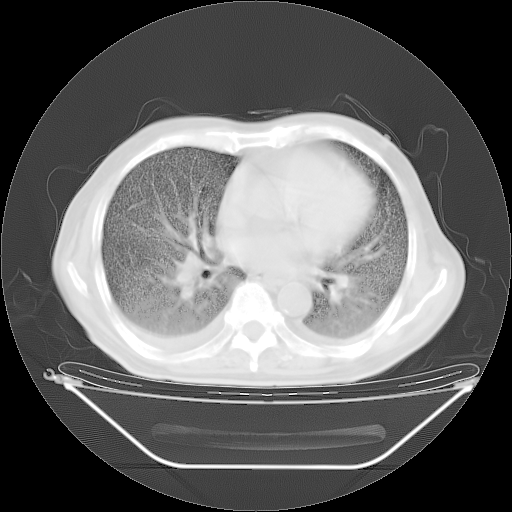

今天复查肺部CT,发现双肺广泛磨玻璃样改变。所以我把3月19日和5月9日相隔50天的肺部CT上传。请大家会诊。

5月9日肺部CT(在4月27日齐鲁医院肺部CT描述部分肺组织磨玻璃样改变,12天后肺组织广泛磨玻璃样改变)

2009年5月9日肺部CT

大致读了系列胸部CT:纵隔窗无明显异常,肺窗:从4、27至今:主要是双肺中下野外带可见毛玻璃样改变,目前处于急性肺泡炎阶段,至于原因考虑1、结替组织或胶原血管性疾病所致?2、恶性疾病如恶组在肺部所致的表现或细支气管肺泡癌?3、药物或其它原因如肺蛋白沉着症所致肺泡炎目前不太可能?总之,明天就去请我院的呼吸科、感染科、血液科和临免专家会诊哈。